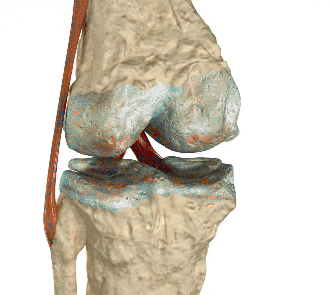

A világon élő emberek 80% -a ízületi betegségben szenved

Az ízületi megbetegedések minden oka még az orvosok számára sem ismert. Ezek fő megsértésének minősül az emberi immunrendszer. Azonban számos tényező növeli az ízületi betegségek megjelenésének és fejlődésének kockázatát:

A csontbetegségek világszervezete szerint a világon élő emberek 80% -ának van ízületi problémája. A legrosszabb az, hogy az ízületi betegségek bénuláshoz és fogyatékossághoz vezetnek. Napjainkban egyetlen megoldás létezik, amely különbözik az előtte lévő összes eszköztől. Ez a HondroLife.

HondroLife - egy új szó a porc és az ízületek helyreállítására idős embereknél. A készítmény kiváló hatékonysággal rendelkezik, és sok betegnek segít jelentősen csökkenteni az ízületek, izmok, csontok fájdalmas tüneteit és gyulladását.